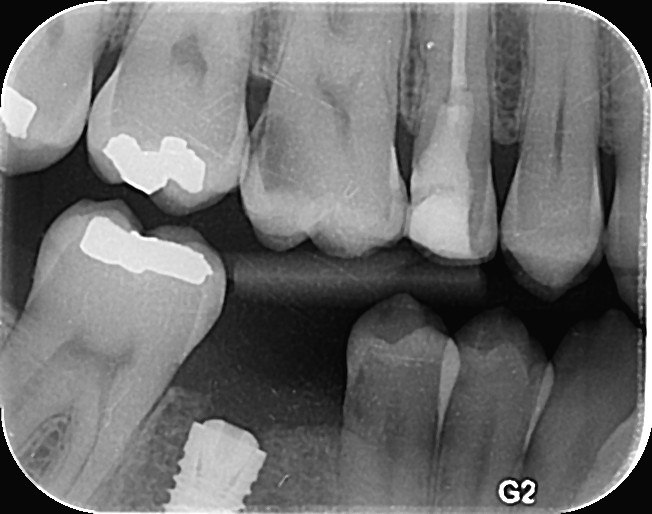

Question 11: Which materials cannot be seen in the print of the X ray?

Question 12: What option cannot be selected for the following X ray?

Question 13: What option cannot be selected for the following X ray?

Question 14: Which surface shows overhang restoration?

Question 15: Which surface shows overhang in the restoration?

Question 16: Which surface shows overhang?

Question 17: Which surface shows overhang?

Question 18: Which surface shows overhang?

Question 19: Which option can be chosen for the tooth # 3.6?

Question 20: which tooth shows defective resotration?

Question 21: What option is can be selected for distal tooth # 4.6?

Question 22: Which surface shows defective restoration?

Question 23: Which surface shows overhang?

Question 24: Which surface shows defective restoration?

Question 25: Which surface shows open margin?